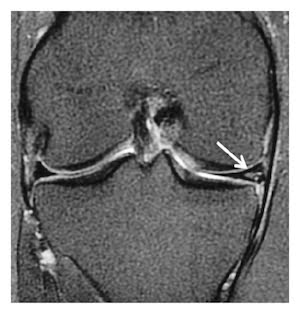

- Αδυναμία κίνησης του γόνατος ή κλειδωμένο γόνατο – ενδεικτικό ρήξης μηνίσκου δίκην λαβής κάδου (bucket handle tear), η οποία χρήζει πιο εσπευσμένης αντιμετώπισης.

- Συρραφή μηνίσκου: στην περίπτωση αυτή, ο μηνίσκος επιδιορθώνεται με ράμματα με τη βοήθεια ειδικών μικροσκοπικών αρθροσκοπικών αγκυρών (all-inside arthroscopic meniscal repair). Συρραφή επιδέχονται οι οξείες (πρόσφατες) ρήξεις σε νέους ασθενείς, οι οριζόντιες ρήξεις, οι κάθετες περιφερικές ρήξεις και οι ρήξεις bucket handle εφόσον έχουν διαγνωστεί εγκαίρως.

Ειδική περίπτωση αποτελεί το κλειδωμένο γόνατο που σχετίζεται με ρήξεις bucket handle. Είναι καθοριστικής σημασίας να γίνει γρήγορη διάγνωση με MRI – πρέπει να κάνετε μαγνητική εντός μερικών ημερών! Δεν πρέπει να περιμένει για την επόμενη εβδομάδα γιατί η πιθανότητα να είναι δυνατή η συρραφή μειώνεται δραματικά, ενώ ταυτόχρονα αυξάνεται κατά πολύ η πιθανότητα εκδήλωσης πρώιμης αρθρίτιδας.